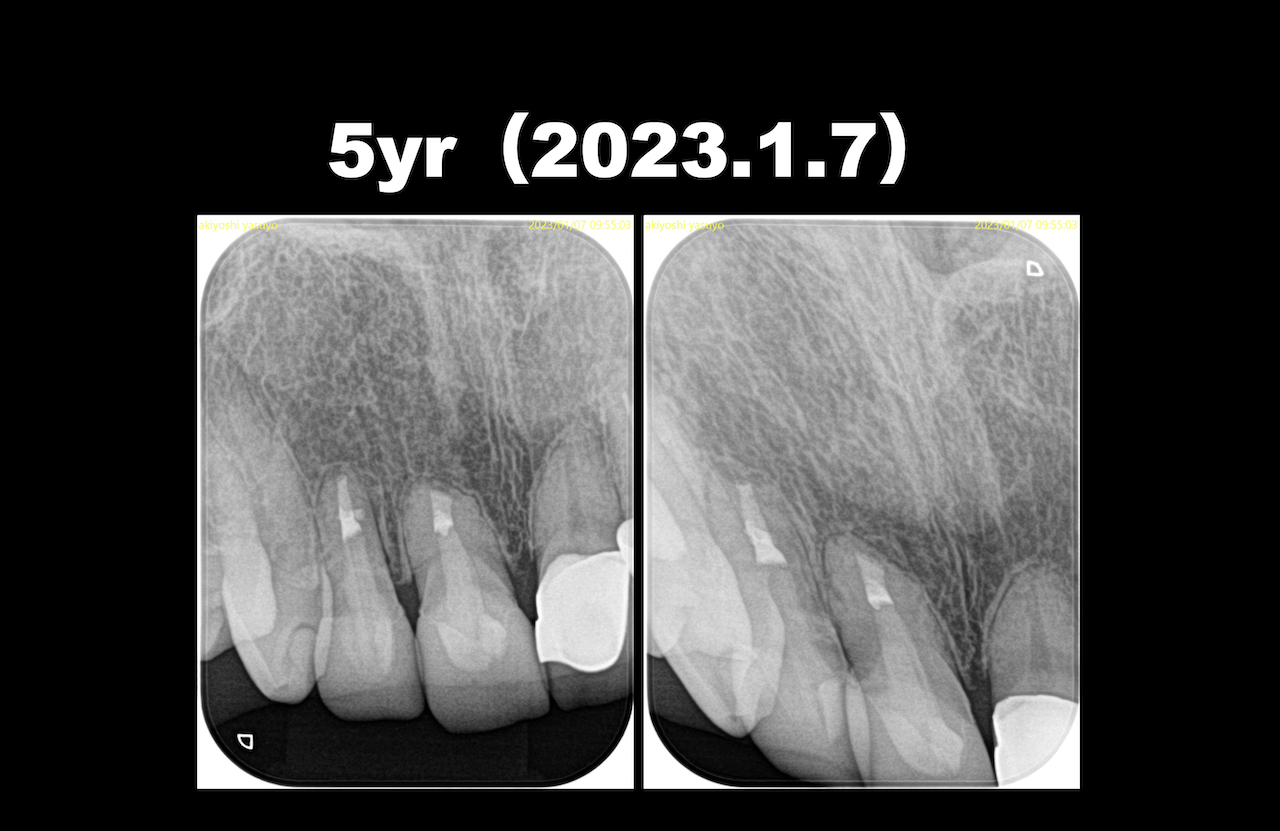

ここから1年経過して以下のようになった。

歯周病がなければこのようになる確率が90%である。

それは何度も言うように、私がでなく過去の研究で、だ。